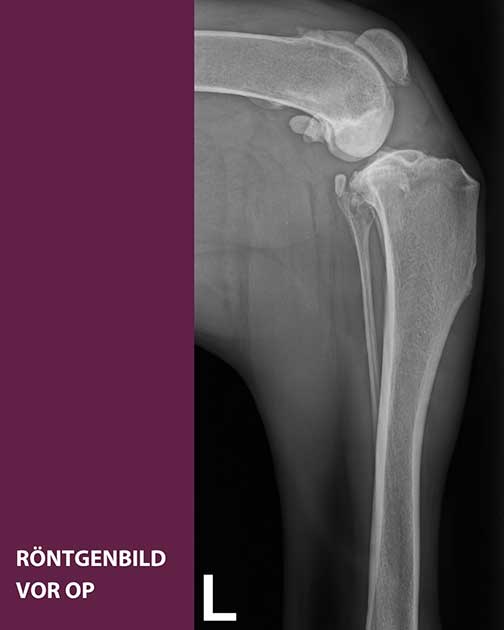

TPLO bei einer Riesenrasse: Die Röntgenbilder zeigen den Kreuzbandriss von Dogge Apollo – einmal vor, einmal nach der Operation.

In unserer orthopädischen Spezialsprechstunde wurde schließlich die Diagnose gestellt: Kreuzbandriss im linken Kniegelenk. Dabei handelt es sich um die häufigste orthopädische Erkrankung bei Hunden, die in unserer Klinik zur Routine gehört. Doch Apollos Körperbau stellte besondere Anforderungen: Neben chirurgischer Erfahrung und Präzision war hier aufgrund des hohen Körpergewichts eine spezielle Anpassung der Standard-Operationsmethode notwendig.

Klinikleiter Dr. Zahn, der die Operation selbst durchführte, entschied sich für die sogenannte TPLO – ein bewährtes Verfahren, bei dem der Schienbeinkopf durchtrennt, in seiner Neigung verändert und mit einer speziellen Metallplatte fixiert wird. Ziel ist es, die Biomechanik des Kniegelenks so zu verändern, dass es auch ohne funktionierendes Kreuzband stabil bleibt.

In Apollos Fall wurde der Schienbeinkopf um rund 30 Grad rotiert. Während bei normal gewichtigen Hunden eine Knochenplatte ausreicht, kamen bei Apollo zwei Platten zum Einsatz – für maximale Stabilität der Riesenrasse.